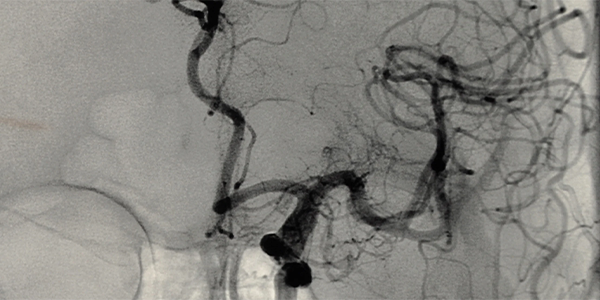

• Conventional Angiography: The standard method described above.

Cerebral angiography is usually performed in a radiology laboratory. During the procedure, the patient lies on a table. The area where the intervention will be performed (groin or arm) is cleaned and local anesthesia is applied. Once the anesthesia takes effect, a thin needle is used to access an artery, and a catheter is inserted. The catheter is guided to the brain’s blood vessels under X-ray imaging. Contrast material is injected into the vessels through the catheter, and X-ray images are taken. At the end of the procedure, the catheter is removed, and pressure is applied to the insertion site to stop bleeding. The patient is monitored for a few hours.

The results of cerebral angiography are evaluated by a radiologist. The radiologist examines the images to assess the structure of the brain’s blood vessels, blood flow, and any abnormalities. The results are used to determine the patient’s treatment plan.